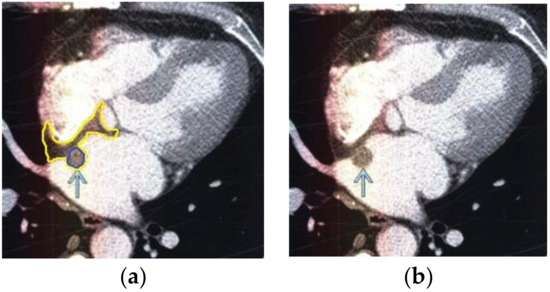

The contour extraction method was used to identify cancerous areas that, after applying the model to eliminate mixed noise, had an increased contrast of volumetric heterogeneous formations in the region of the heart [27]. This method was developed by the authors when analyzing thermal images to assess the condition of the coronary vessels of the myocardium under cardiopulmonary bypass. The contours of the cancerous regions in the examples used for applying the model to eliminate mixed noise (Figure 4, Figure 5, Figure 6, Figure 7, Figure 8 and Figure 9) are highlighted in yellow and they represent the visual boundary of the distribution of volumetric heterogeneous formations.

• For a patient with a history of lung cancer: during MRI with contrast enhancement, the volumetric formation of a heterogeneous structure in the left ventricle was determined (Figure 4).

• For a patient with a history of melanoma: during MRI with contrast enhancement, a volumetric formation adjacent to the atrial septum was visualized in the left atrium (Figure 5).

Figure 4. Heart MRI: (a) image with white noise and (b) denoised image with contrast enhancement of volumetric heterogeneous formation.